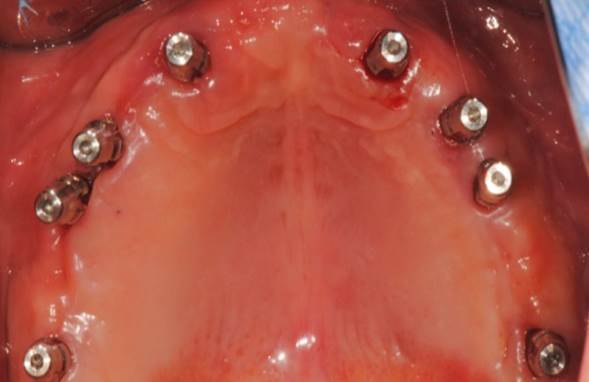

Clinical case: Extraction of all teeth in upper maxilla,

immediate implant placement, & provisionalization

- Courtesy of Dr. Iulian Filipov, Romania -

Keywords

AnyRidge, immediate placement, immediate provisionalization, maxillary fully edentulous case, initial stability, edentulous, Dr. Iulian Filipov, R2GATE, MEGA ISQ

Products:

AnyRidge implant system, Mega ISQ, R2GATE